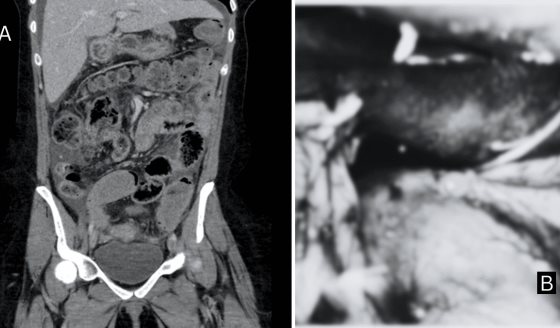

En cuanto al diagnóstico, si se sospecha un colangiocarcinoma, el médico puede realizar diversas pruebas como análisis de función hepática y del marcador tumoral CA 19-9, que pueden sugerir la presencia de cáncer.

También se emplean estudios por imágenes como ecografía, tomografía computarizada y resonancia magnética. En algunos casos se utiliza la colangiopancreatografía retrógrada endoscópica para observar directamente los conductos y tomar muestras o biopsias.